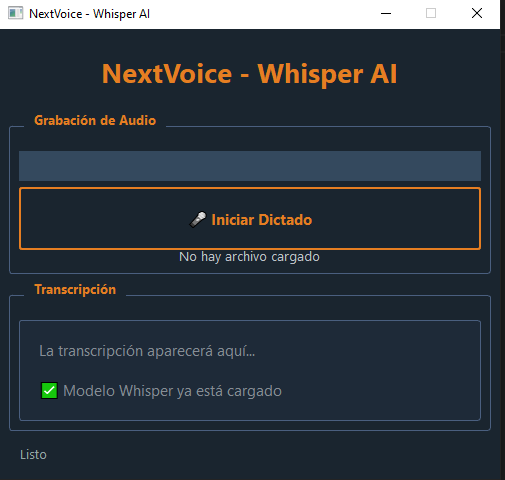

Asistencia con Inteligencia Artificial

NextRIS incorpora asistencia por IA integrada al proceso de redacción:

– Comparación automática del borrador con informes anteriores del mismo paciente para detectar cambios evolutivos

– Sugerencias basadas en el historial radiológico del paciente

– Mayor consistencia clínica entre estudios sucesivos y reducción del tiempo de redacción